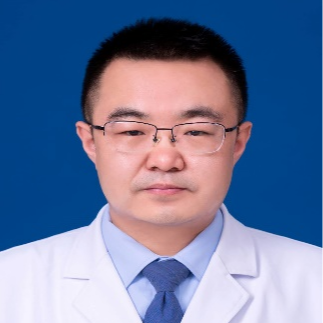

专家简介

主任医师

纪文军

博士毕业于首都医科大学附属北京天坛医院,师从我国神经介入奠基人吴中学教授。目前任西安交通大学第一附属医院榆林医院院务委员、脑科医院院长、神经外科二病区主任,兼任10多家省级以上学会的委员和常委,榆林市神经介入学会主委、榆林市脑血管病质量控制中心主任。擅长脑血管病的神经介入诊疗、重型颅脑损伤与脑出血的综合救治、颅内肿瘤的微创治疗等。在区域内率先开展了颅内动脉瘤栓塞、颅内血管狭窄支架植入、颅内大血管闭塞取栓等各类神经介入手术,内镜下垂体瘤切除等神经内镜手术。目前已在Stroke,World Neurosurgery等国际神经外科与脑血管病杂志发表SCI论文15篇;在《中华神经外科杂志》、《中华医学杂志》、《中国微侵袭神经外科杂志》、《中国卒中杂志》等发表核心论文40余篇。参与国家自然科学基金及省部级基金4项,主持陕西省自然科学基金等省级基金项目3项,主持榆林市科技项目3项。获得陕西省科技进步奖2项,榆林市科技进步奖7项。参编著作3部,参译著作3部。获得榆林市青年科技奖、榆林市优秀科技工作者、榆林市有突出贡献专家、榆林市十大杰出青年、榆林市十大科技创新人物等诸多荣誉称号。